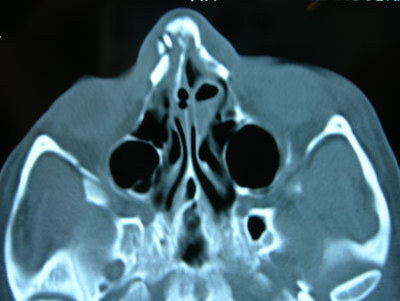

А такое было? Вот я собирал фотографии своих друзей. Точнее, фото их носов. Ещё точней, рентгенограммы их сломанных носов.

Молодость была бурной дивной.